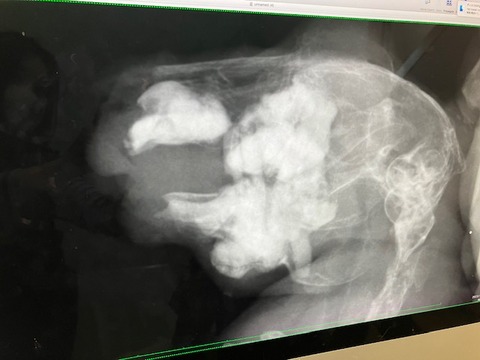

切歯不正咬合で通院はたくさんしましたが、

レントゲンなどは当初の去勢手術以降、機会がなかったので、

血液検査とともにしっかり健診させていただきました。

レントゲン

歯根への影響も見られず、共に良好でした